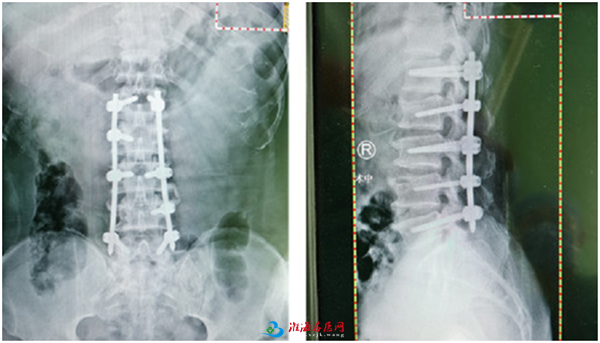

日前,徐州仁慈医院脊柱科就借助天玑骨科手术机器人,又完成一例多发性腰椎骨折手术,通过机器人辅助定位几个“钉眼”,成功完成手术,避免了常规手术通常要开的25厘米创口。骨科机器人的参与让原本复杂的手术更加精准、微创、安全。

“我们在全麻下进行了机器人辅助腰椎骨折闭合复位内固定术。手术时,机器人的置针非常精准,按术前规划和医生指令准确执行。相比常规手术,机器人辅助下的脊柱手术切口更微创。”有20余年骨科手术经验的尚军主任介绍,像这台多发性腰椎骨折手术,以前的常规处理通常要开25厘米大口子,植入钢板,创伤大、术中出血多、术后恢复慢,容易导致后期肌肉瘢痕化,而且脊柱周边神经多,创口大容易伤到神经造成截瘫。但是用了这台骨科手术机器人,通过微创手术,每个切口仅1厘米左右,在机器人定位下打入8根钉,非常精准、也比较安全,同时术中出血少,术后恢复快,减轻患者和家人压力。